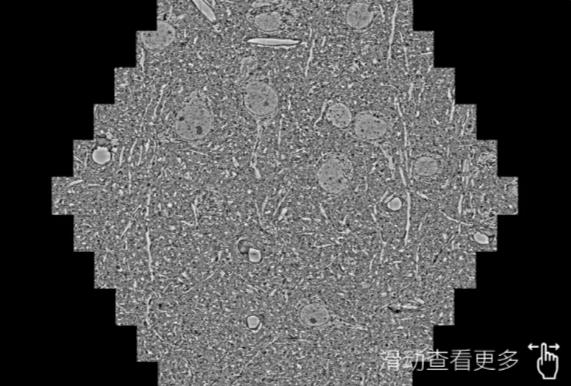

鼠脑切片。左图使用天门蔡司天门扫描电镜MultiSEM706对165μmx143pm面积区域成像,耗时仅需1.5秒。右图为鼠脑切片中30μm区域放大效果。样品由芝加哥大学B.Kasthuri提供。

使用蔡司高速天门扫描电镜MultiSEM对1mm²人脑皮层组织进行高分辨成像,并对其中的各种细胞结构进行三维重构分析。左图展示了2x3mm²组织平面中锥体神经元的三维重构效果。右图显示了局部体积神经元三维重构。图像由哈佛大学chtman实验室提供,渲染图由D. Berger 制作。